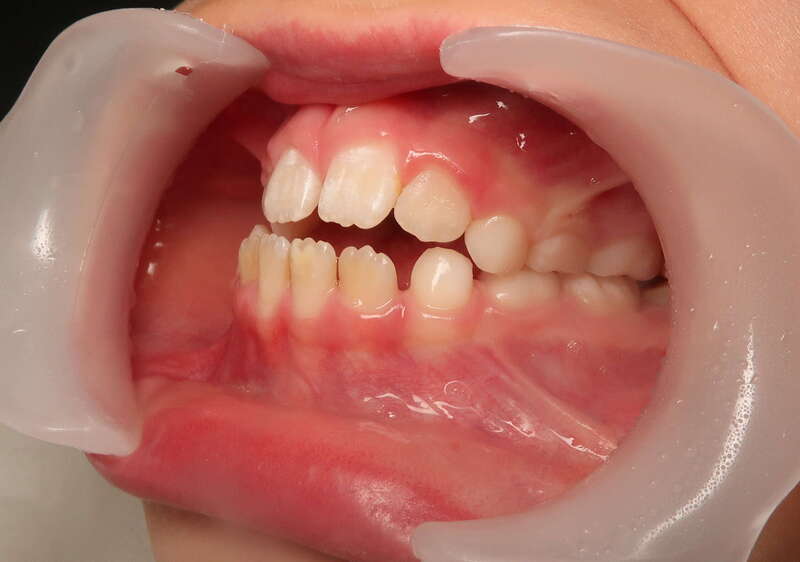

Cas n°1 traité par aligneurs (interception) - enfant

Ce cas d’interception chez un enfant de 8 ans démontre l'efficacité des aligneurs pour corriger des troubles fonctionnels précoces. Le diagnostic présentait des inversions d'articulé provoquant une déviation de la mandibule vers la gauche et un décalage des milieux.

Grâce à une coopération exemplaire et un traitement totalement indolore, l'expansion de l'arcade a permis de recentrer la mâchoire. Cette intervention a littéralement remis la croissance sur les rails, neutralisant le risque d'asymétrie faciale squelettique.

Avant

Après